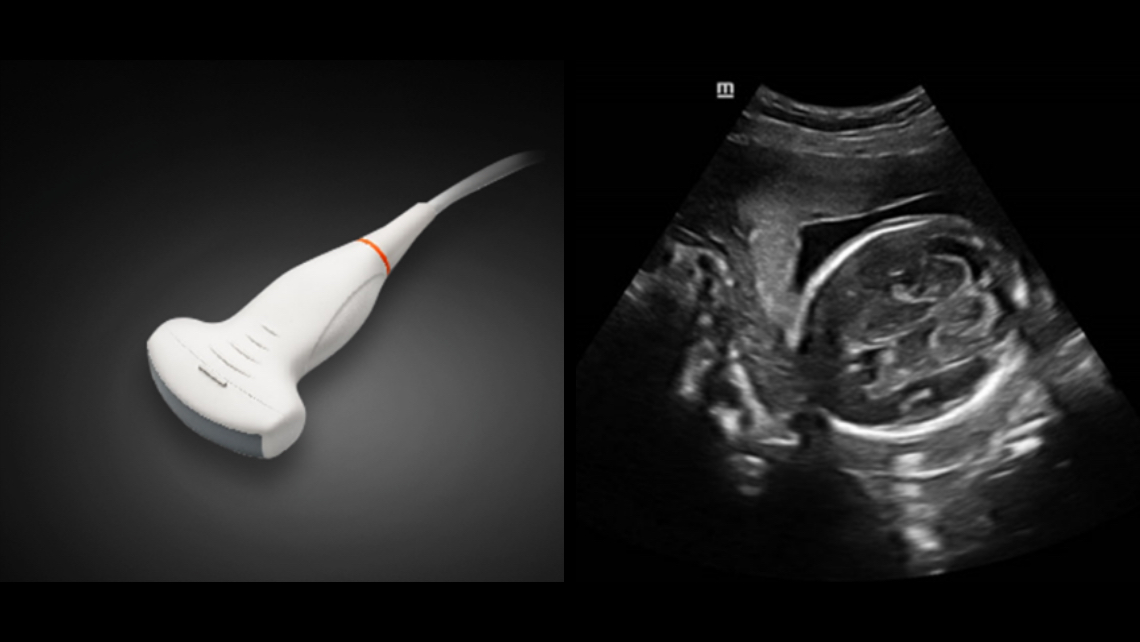

DE11-3E Dual-Volume Solution

DE11-3E Dual-Volume Solution

SC5-1N & SD8-1E

Images cliniques